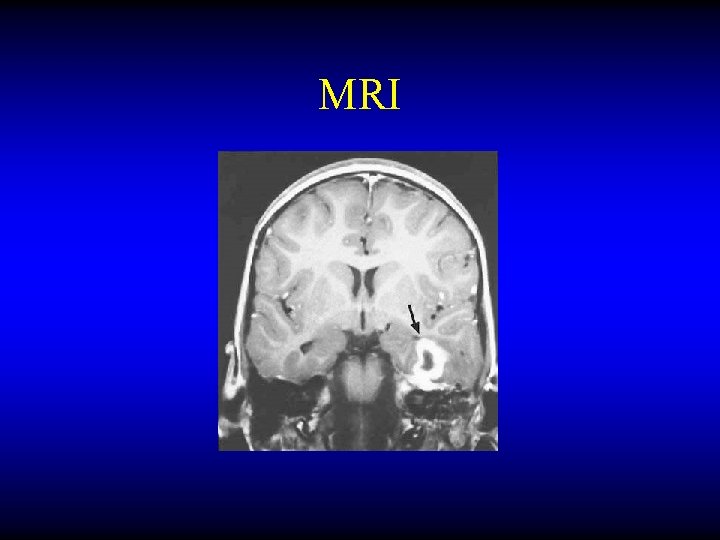

OTOGENIC BRAIN ABSCESS Diagnosis • • CT MRI LP Burr hole needling

MRI